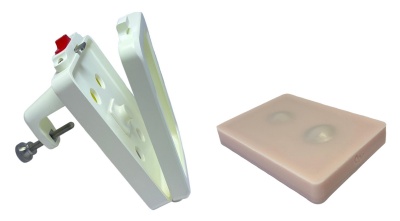

儿童腰椎穿刺训练模型

儿童腰椎穿刺训练模型

小儿腰椎穿刺训练模型(带电子监测)

小儿腰椎穿刺训练模型(带电子监测)

新生儿腰椎穿刺训练模型

新生儿腰椎穿刺训练模型